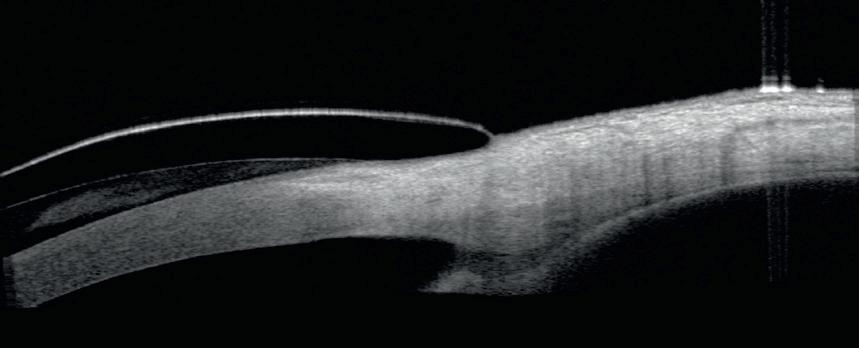

CASE STUDY:

Fitting a highly toric and asymmetric ocular surface using current lathe technology

BACKGROUND

A 25-year-old female with history of severe aqueous deficiency dry eye and f lamentary keratitis following numerous ocular reconstruction surgeries since infancy for excision of benign neoplasm of lacrimal gland and coloboma of lid repair presented for a PROSE scleral lens consultation. Te patient complained of ocular discomfort and poor vision, recalcitrant to all prior therapies including periodic amniotic membranes. ODsc: 20/150 (PH 20/60) OSsc: 20/30-2 (PH 20/25+2)

PLAN

Improve vision, comfort, and support the ocular surface with a scleral lens. To ft around the temporal conjunctival obstacle, the diameter of the lens must be either small enough to avoid the anatomical obstacle entirely (and likely necessitating a notch) or be large enough to cover the obstacle. A larger diameter design was pursued to ft over the anatomical obstacle and allow better coverage of the desiccated ocular surface.

TRIAL LENS SELECTION

• 18.5mm/2.88 sag/8.0 BC/+0.25 sph/0.35mm bitoric

• VA: 20/80+2

• Over-refraction: +3.00 sphere; 20/40-2

an 8-meridian toric design was pursued. Sagittal depth was reduced by 300 microns and additional haptic adjustments were made to address areas of edge li f

LENS DESIGN # 1

• 18.5mm/2.58 sag/ 8.0 BC/ +3.25 sph/ 8-meridian 1.12mm toric (steepest meridian at 7:30)

• VA: 20/40-2, without improvement with over-refraction

• Residual compression over the temporal elevated conjunctiva was evident. Centration of the lens greatly improved. Tere was adequate and improved corneal clearance, with resolution of the inferior tear prism. Residual inferior temporal edge li f was noted.

LENS DESIGN #2

• 18.5mm/2.58 sag/8.0 BC/+3.25 sph/ 8-meridian 1.32mm toric (steepest meridian at 7:30/ custom temporal channel (135 – 190^, 250 microns of depth)

• VA: 20/30-1, without improvement with over-refraction

• A channel was added to the temporal aspect and the inferior temporal edge was steepened.

RESULTS

Te patient continued with daily scleral lens wear, with signifcant improvement in comfort and vision, with resolution of flamentary keratitis. Given the highly toric and asymmetric nature of the ocular surface, necessary lens adjustments could only be achieved with access to advanced high precision FT3 technology provided by our lathe vendor. With appropriate precision lathe technology, the range and customization of ftting is boundless.

Te initial trial lens was applied and demonstrated a poor ft. Necessary adjustments to obtain an optimal ft were implemented with utilization of thorough slit lamp evaluation and implementation of PROSE scleral lens customizations. Tere was notable compression overlying the temporal elevated conjunctiva with associated inferior temporal edge li f . Mild edge li f was also noted nasally, inferiorly and superiorly. Te apical vault was also over 500 microns and demonstrated inferior decentration as evident by the inferior tear prism. Two scleral lenses were designed. T e highly irregular ocular surface and focal signi f cant inferior temporal edge li f necessitated at least 1 mm of steepening. To achieve this in this oblique meridian,